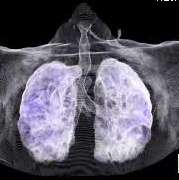

Stereotactic body radiation therapy (SBRT) is a treatment procedure similar to central nervous system (CNS) stereotactic radiosurgery, except that it deals with tumors outside of the CNS. A stereotactic radiation treatment for the body means that a specially designed coordinate-system is used for the exact localization of the tumors in the body (Figure 1) in order to treat it with limited but highly precise treatment fields. SBRT involves the delivery of a single high dose radiation treatment or a few fractionated radiation treatments (usually up to five treatments). A high potent biological dose of radiation is delivered to the tumor, improving the cure rates for the tumor, in a manner previously not achievable by standard conventional radiation therapy (Figure 2).

This is a specialized type of external beam radiation that allows highly precise delivery of high doses of radiation to small targets. Typically treatment with this technique is completed in 3–5 treatments over the course of 1–2 weeks. This is opposed to the daily standard external beam radiation treatment that is typically given over the course of multiple weeks.

SBRT requires accurate and custom mapping for each individual patient's anatomy and organ motion so that we may be able to optimally target the tumor and simultaneously spare the surrounding normal tissue. We utilize any and all potential imaging modalities such as PET, MRI, CT, as well as other novel imaging platforms to localize the tumor in four dimensions. It requires highly sophisticated radiation delivery systems not available in most radiation oncology practices. More importantly, it requires clinical expertise and experience which allow our expert radiation oncologists to make sound treatment judgments regarding a recommendation for SBRT. In addition, you can be assured that our expert team will competently follow-through with an efficacious and safe SBRT radiation plan at the time of treatment. Instead of several weeks of conventional radiation therapy, patients complete their SBRT in a short-period of time, usually over a one week period, minimizing the inconvenience of daily trips to the radiation oncology facility.